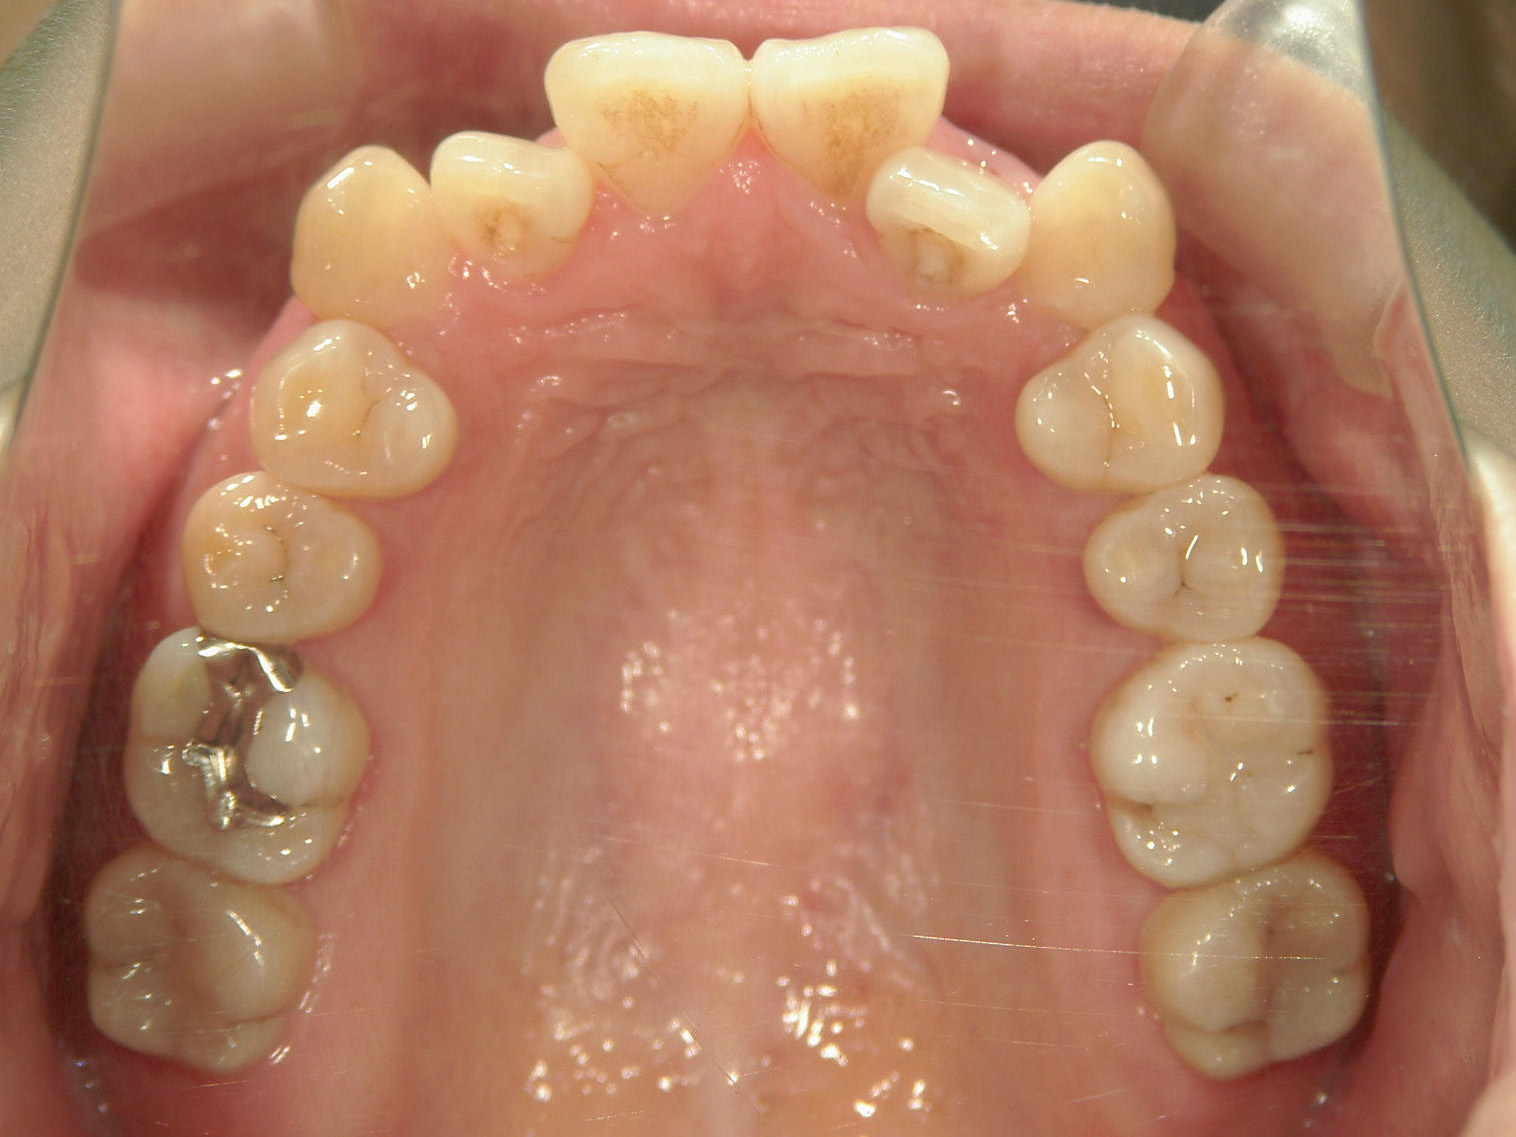

プチワイヤー矯正 症例(53)

主訴: 前歯の歯並びが気になる。

スライスカットを併用。

カテゴリー : ガタガタ(叢生)